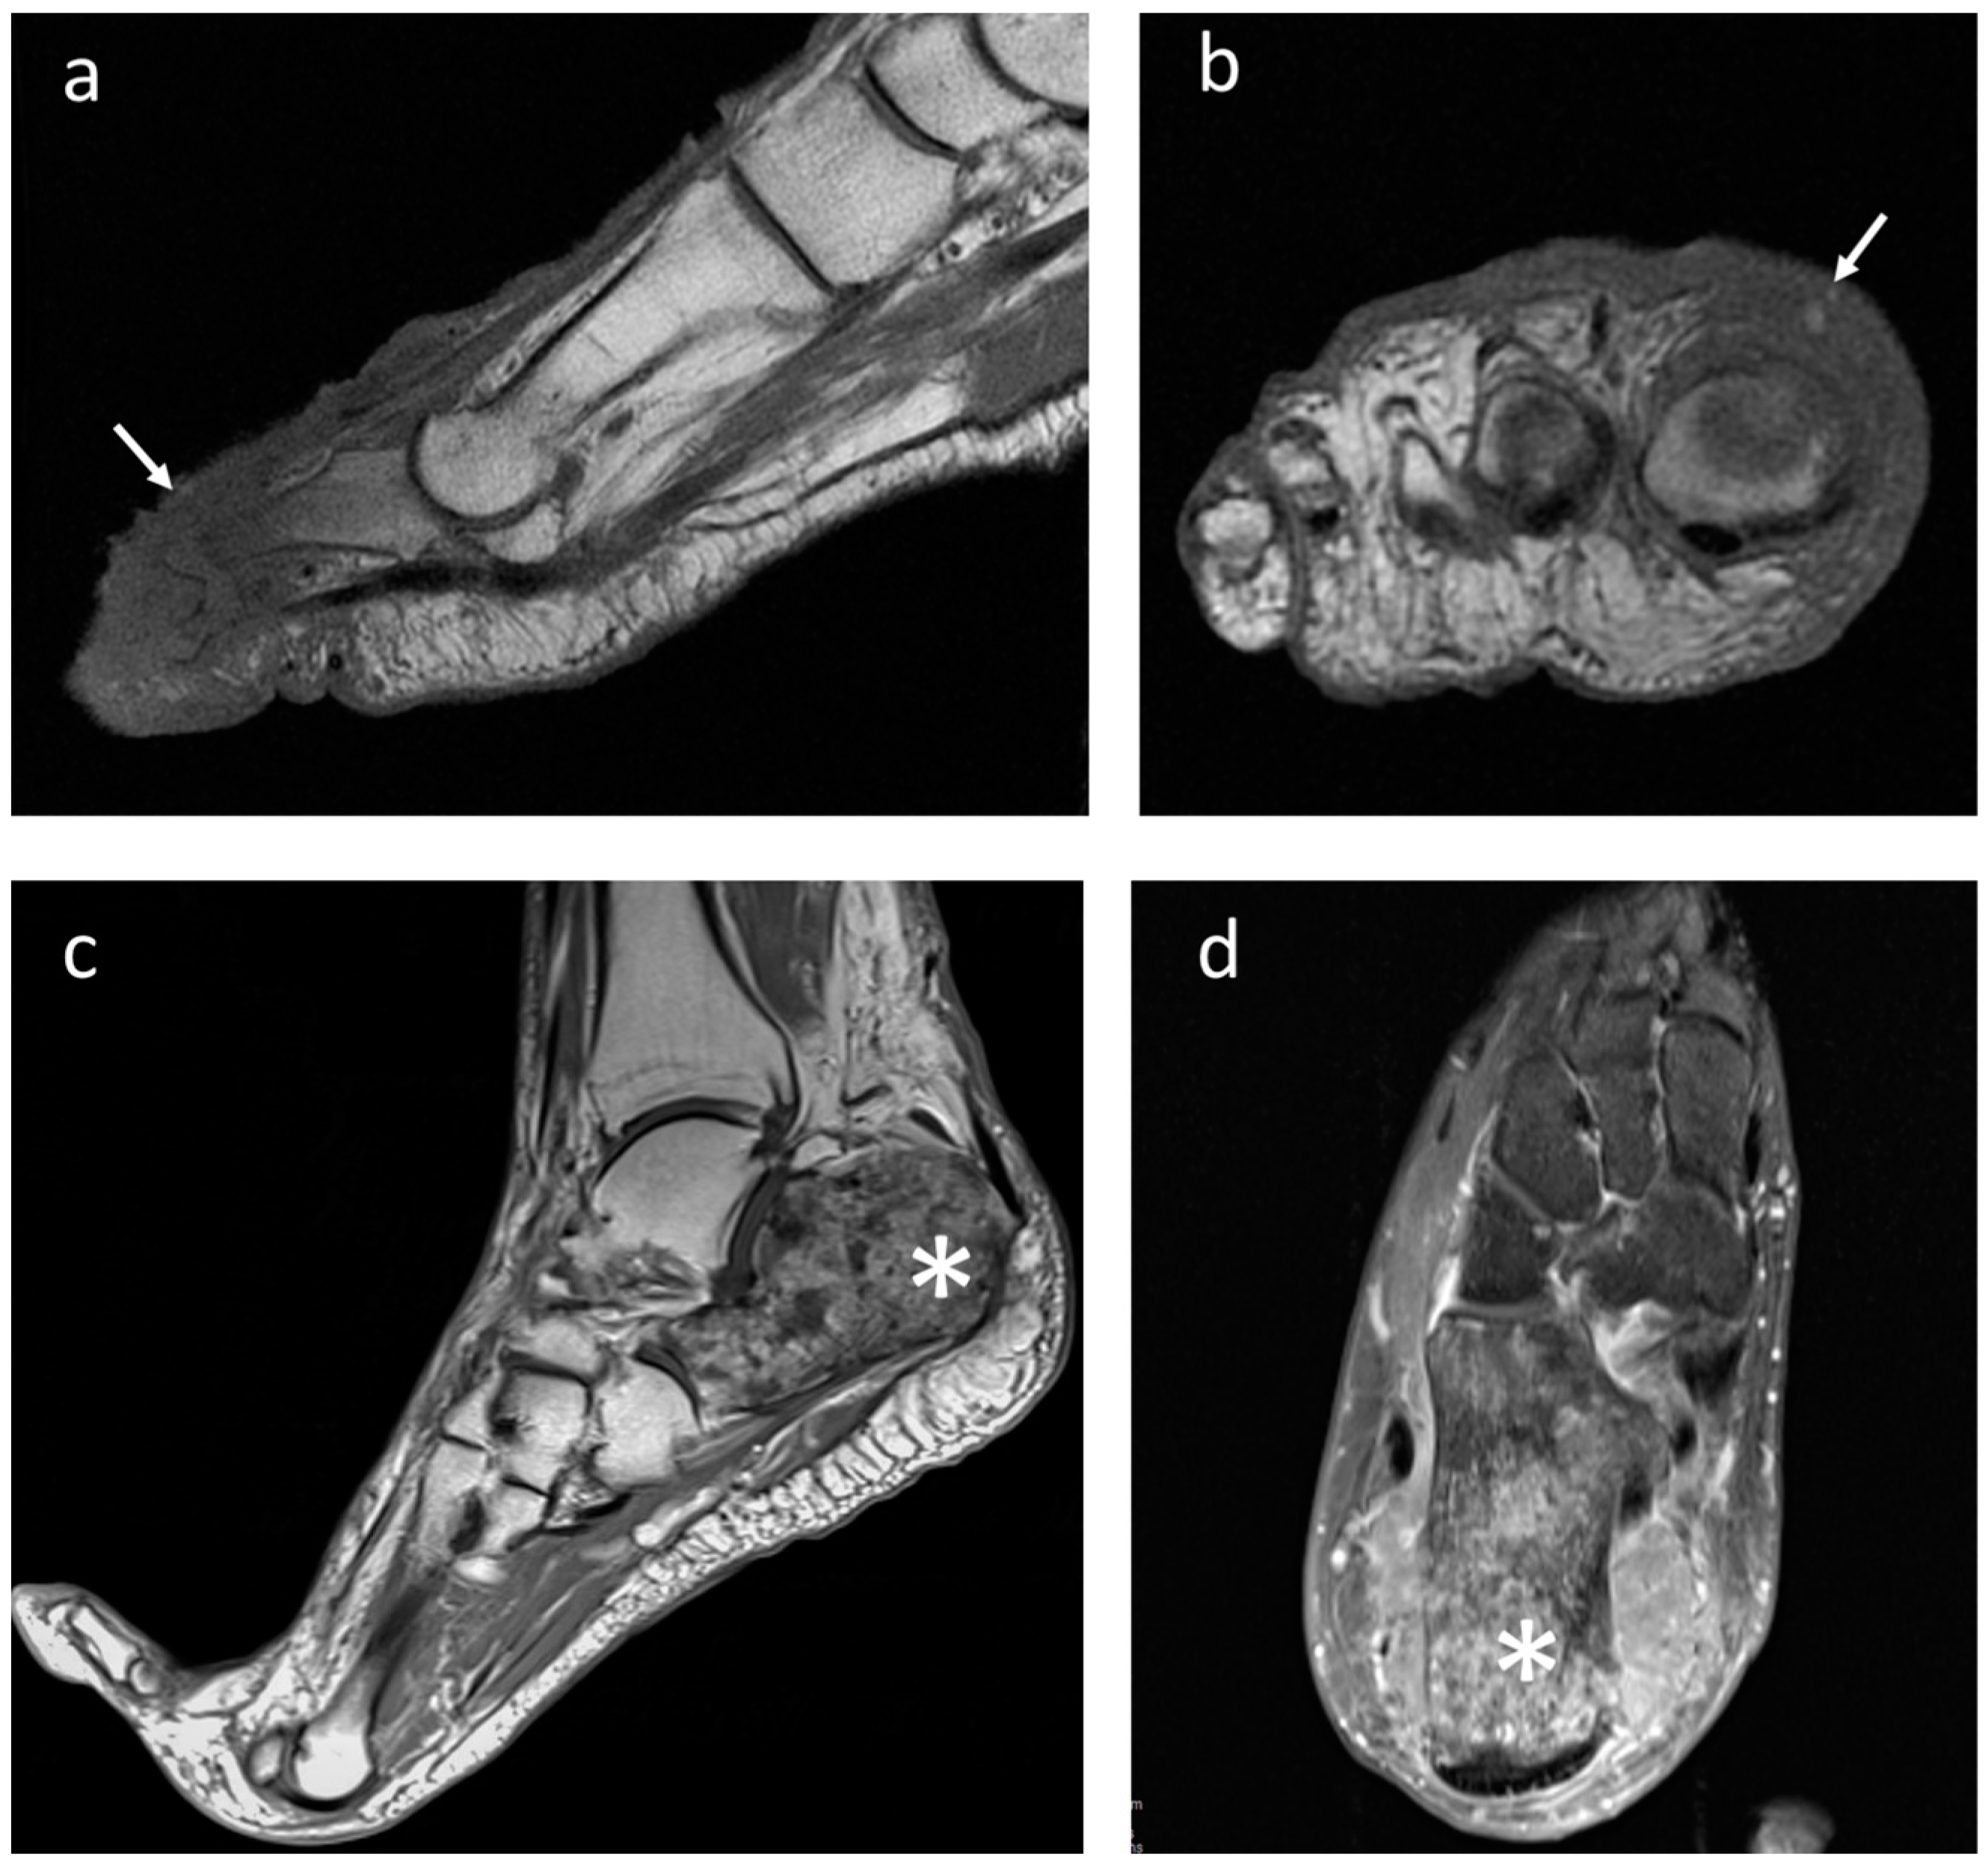

4.1. Melanoma

4.3. Synovial Sarcoma

4.4. Clear-Cell Sarcoma

4.5. Rhabdomyosarcoma

4.6. Leiomyosarcoma

4.7. Liposarcoma